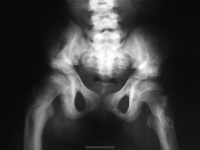

③四肢:“手镯”及“脚镯”;开始行走后,(“O”型)或(“X”型)腿,长骨可发生青枝骨折。

本病主要是引起婴儿抬头、坐、站、行走都较晚。关节松弛而有过伸现象,大脑皮层功能异常条件反射形成缓慢,语言发育落后,贫血等症状。 在一些比较严重的佝偻病的患儿中,还会出现其他的骨骼变形,如鸡胸、漏斗胸、X型腿、O型腿、肋串珠、手镯和脚镯等。

2、中度:可见典型的串珠、手镯、肋软骨沟、轻度或中度的鸡胸、漏斗胸、O或X型腿,也可有囱门晚闭、出牙迟缓等明显的改变。

3、重度:可见明显的肋软骨沟、鸡胸、漏斗胸、脊柱畸型、O或X型腿、病理性骨折等严重改变。

2、激期:常见于3个月至2岁的小儿。有明显的夜惊、多汗、烦躁不安等症状。同时可有中度的骨骺改变体征。X线片可见临时钙化带模糊消失,干骺端增宽,边缘不整呈云絮状,毛刷状或杯口状,骨骺软骨加宽。血钙、血磷均降低,硷性磷酸酶增高。

4、后遗症:多见于3岁以后的小儿。经治疗或自然恢复,症状消失,骨骼改变不再进展。X线及血生化检查正常,仅留有不同程度的骨骼畸形。